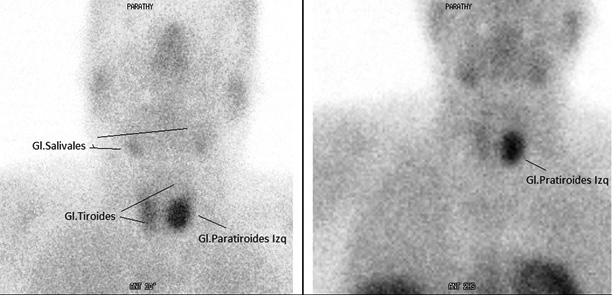

En la ecografía de la glándula tiroides, se observó una lesión nodular sólida y heterogénea con una marcada vascularización central y periférica al Doppler de calor. Se complementó el hallazgo con una centellografía paratiroidea con Sestamibi-Tecnecio 99 (Fig. 2). En base a las pruebas de laboratorio e imágenes realizadas, se diagnosticó hiperparatiroidismo primario (HPP) por probable adenoma de paratiroides.

Se observa una zona de aumento de la captación del radiotrazador (Sestamibi-Tc99m) a nivel de la glándula paratiroidea izquierda, la cual se encuentra aumentada de tamaño.